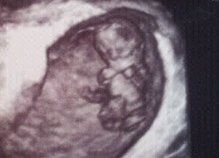

Foto's van mini, hier 9 weken en 4 dagen...